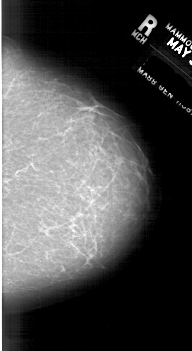

A_1759_1.RIGHT_MLO

RIGHT_MLO LINES 6751 PIXELS_PER_LINE 3841 BITS_PER_PIXEL 12 RESOLUTION 43.5 NON_OVERLAY